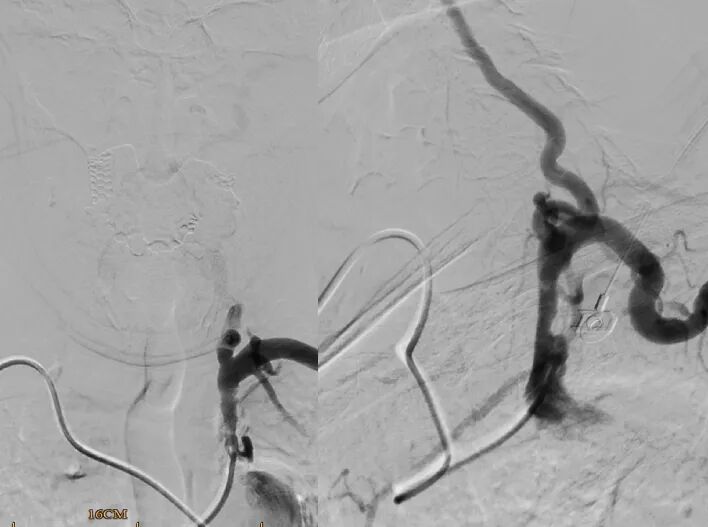

·右侧桡动脉入路造影

明确左侧锁骨下动脉起始部重度狭窄;

同时发现起始部斑块为溃疡斑块。

·球扩后植入9-30自膨颈动脉支架

桡动脉鞘怎么读【REPLAY·周三全桡日】王鹏:双侧桡动脉入路 锁骨下支架_https://www.jmylbn.com_新闻资讯_第18张